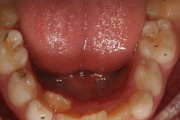

Keel

Infantiilne neelamine